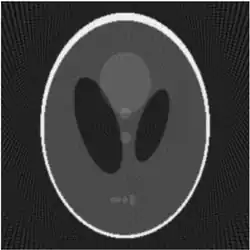

![]() |

| Fantasma de Shepp-Logan; Transformada de Radon; y Transformada de Radon inversa | ||

Existe un algoritmo inverso de la transformada de Radon computacionalmente eficiente para el caso bidimensional llamado retroproyección filtrada. Primeramente consideremos el operador adjunto de :

lo que significa que la imagen original puede ser recuperada del 'sinograma' aplicando un filtro rampa (sobre la variable ) y entonces retroproyectando. Como que el paso de filtrado puede ser implementado de forma eficiente (mediante técnicas de procesamiento digital de señales) y la retroproyección no es más que una acumulación de valores en los píxeles de la imagen, resulta un algoritmo altamente eficiente, por lo que se trata de un algoritmo ampliamente usado.